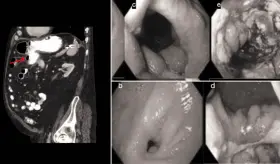

Mediante una tomografía computarizada, los especialistas descubrieron inflamación rectal grave desde el colon descendente distal hasta el recto.

Colonoscopias y biopsias regulares en pacientes con Enfermedad Inflamatoria Intestinal (EII) podrían detectar y prevenir complicaciones con antelación.

Se observaron linfocitos, células plasmáticas, neutrófilos, eosinófilos y perivasculitis granulomatosa a través de un examen histológico.